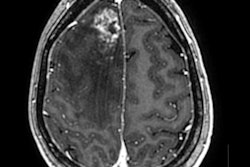

Relaxivity can be thought of as the potency of an MRI contrast agent, according to Kanal, who is director of MR services at the University of Pittsburgh Medical Center. A certain amount of relaxivity is required to prompt anatomical structures to enhance on MRI scans.

A new class of high-relaxivity agents is coming to market that has the potential to provide the same level of enhancement but with less contrast material. This could give radiology facilities the opportunity to use less MRI contrast than previously required, saving money and exposing patients to less contrast.